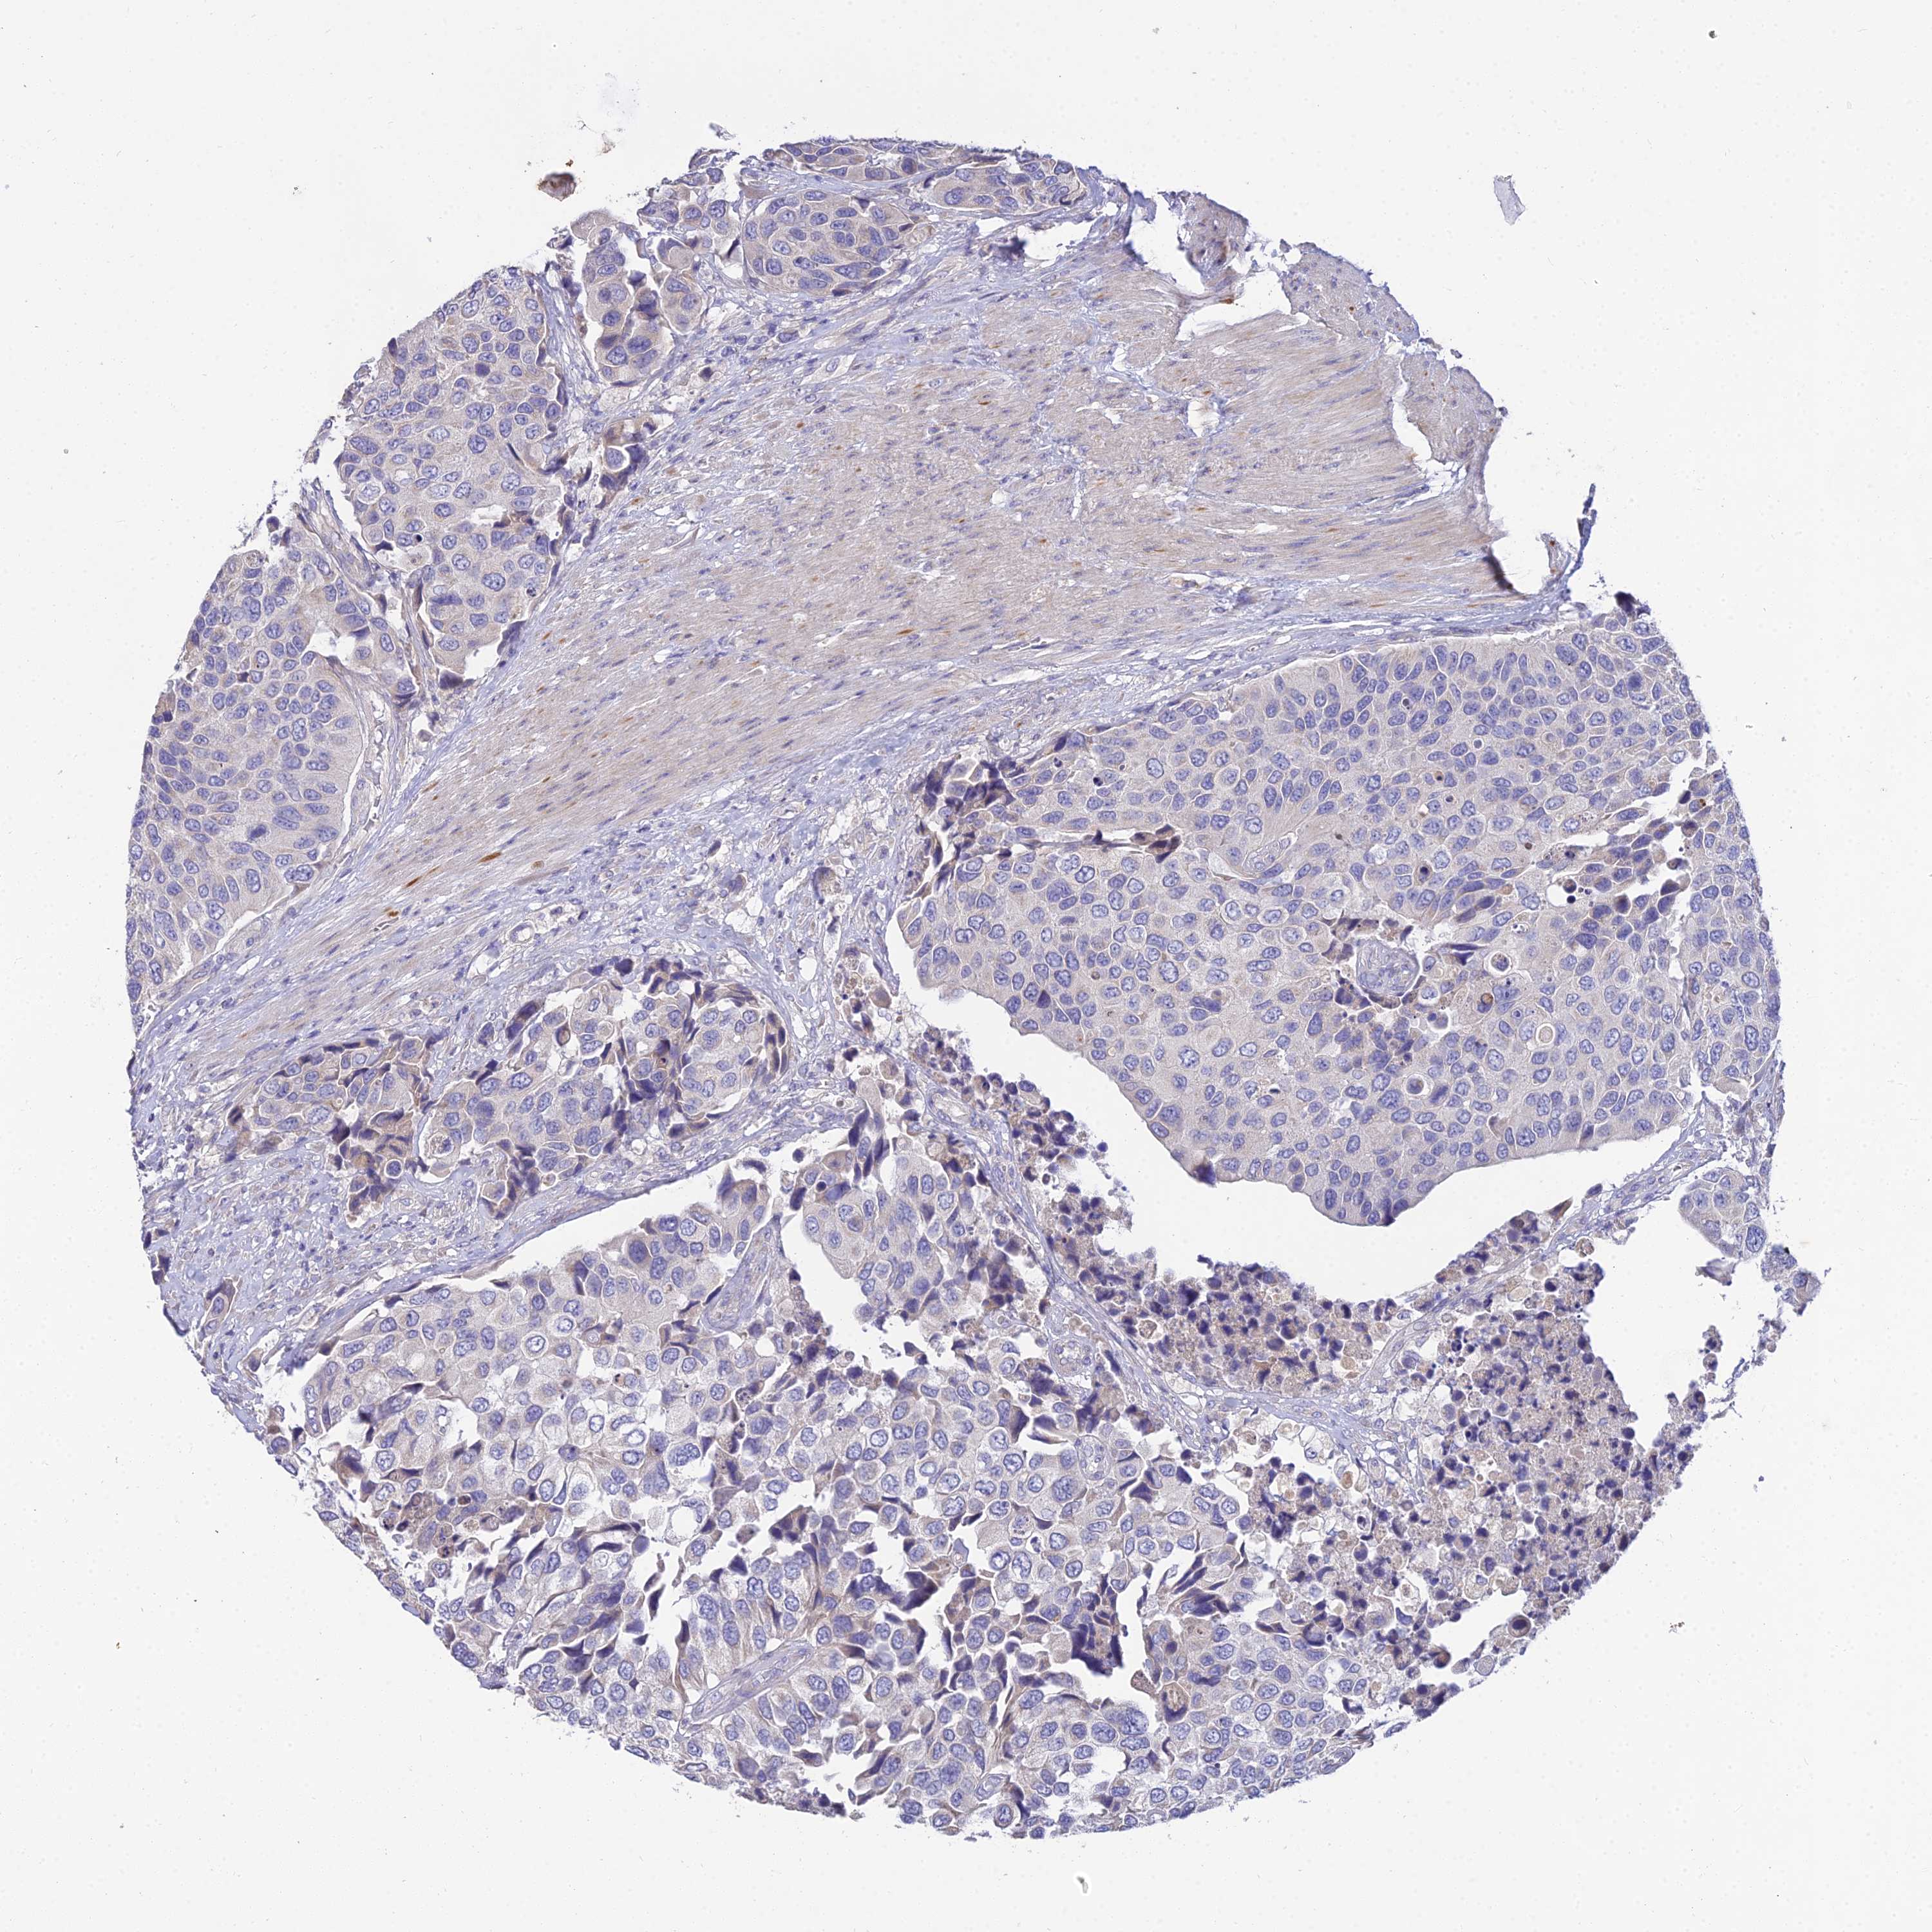

UROTHELIAL CANCER - Protein expressioni

A mouse-over function shows sample information and annotation data. Click on an image to view it in a full screen mode. Samples can be filtered based on level of antibody staining by selecting one or several of the following categories: high, medium, low and not detected. The assay and annotation is described here.

Note that samples used for immunohistochemistry by the Human Protein Atlas do not correspond to samples in the TCGA dataset.

Antibody stainingi

Antibody staining in the annotated cell types in the current human tissue is reported as not detected, low, medium, or high, based on conventional immunohistochemistry profiling in selected tissues. This score is based on the combination of the staining intensity and fraction of stained cells.

Each image is clickable and will lead to virtual microscopy that enables deeper exploration of all samples and also displays staining intensity scores, fraction scores and subcellular localization as well as patient and tissue information for each sample.

Antibody HPA038759

Antibody HPA040515

Antibody HPA045924

Urothelial carcinoma, High grade

Urothelial carcinoma, Low grade